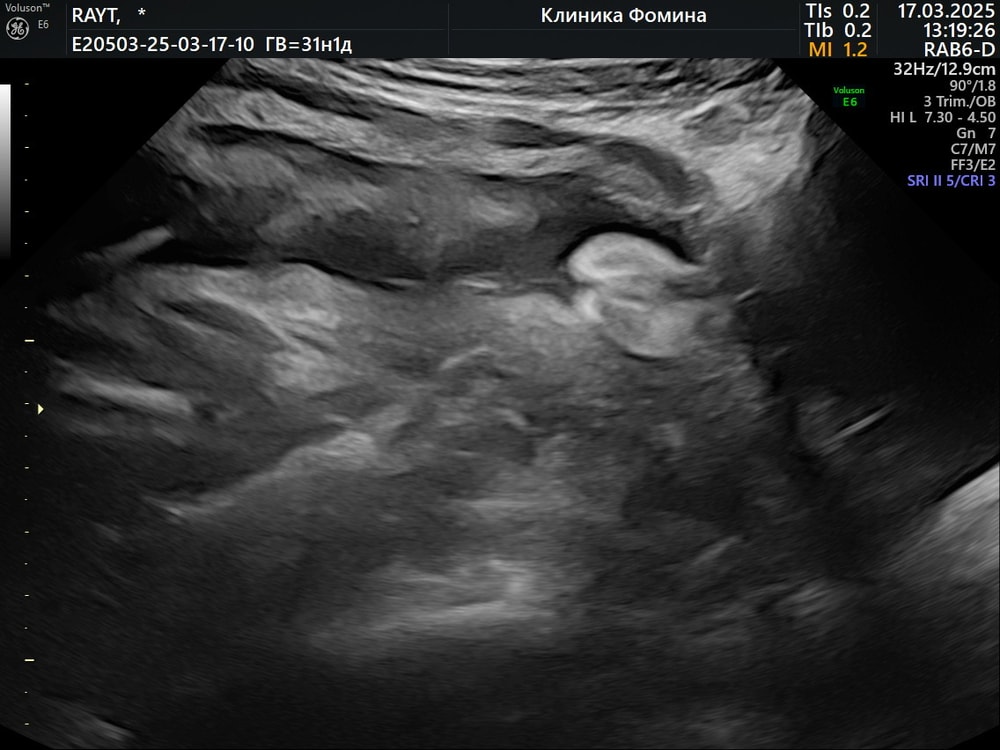

Ну так вам сфоткали девчачий пирожок , пацана тут не видно. Вы принимаете половые губы за яички .нам каждое узи и это больше 10 раз показывали девчачий пирожок . Ни с чем не спутать 😂

Половые губы вижу),но точно не торчок,как у нас)

ИзображениеСобственно вот само фото

Елизавета, девочка, губки пухлые, посредине разрез. Как моя врач говорила, у вашей дочи прекрасное кофейное зернышко, во весь экран показывает, не прячет)))

Елизавета, ИзображениеВот Вам фото мальчика в 28 недель) у вас явная девочка😅